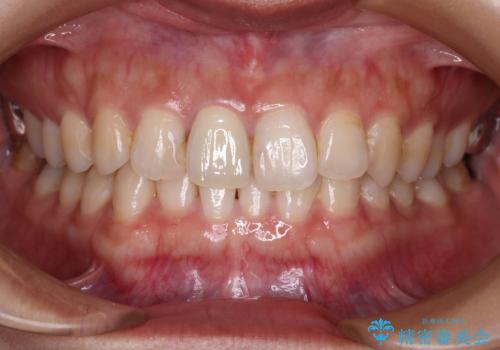

色、形ともに自然で嬉しいですと笑顔で言っていただけました。